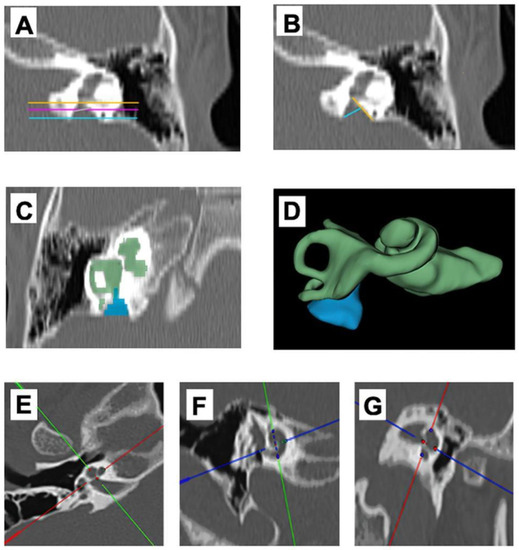

- Alenzi, S.; Dhanasingh, A.; Alanazi, H.; Alsanosi, A.; Hagr, A. Diagnostic Value of 3D Segmentation in Understanding the Anatomy of Human Inner Ear Including Malformation Types. Ear Nose Throat J. 2021, 100 (Suppl. 5), 675S–683S. [Google Scholar] [CrossRef] [PubMed]